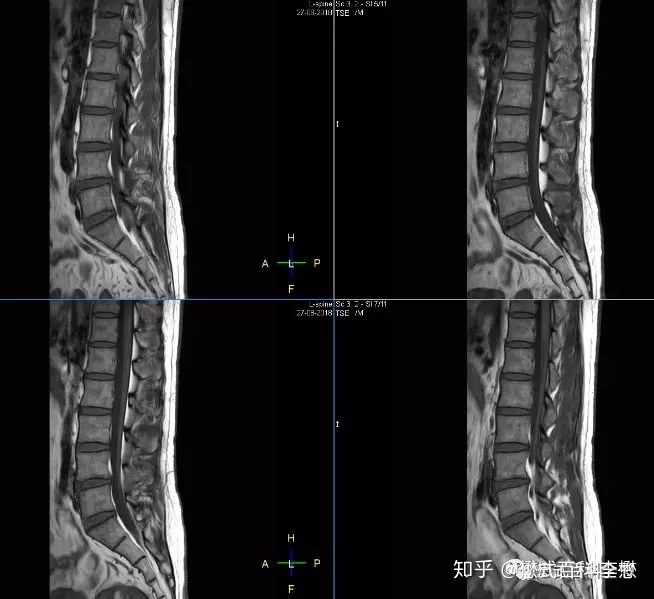

上图,各位临床医生一看肯定知道是脊柱腰椎的矢状位扫描磁共振图。那么这个图到底是哪种加权像呢?是T1WI,还是T2WI,还是PDW?

我们继续利用规律判断,还是先找液体。图像中,脑脊液是黑的,所以这个图是T1WI图。

这里大家注意,我们为什么没有根据脂肪来判断,如图所示,背部脂肪组织在图中是亮的。因为,脂肪组织在T1WI或者T2WI中都是亮的,所以根据脂肪来判断,是不太准确的。